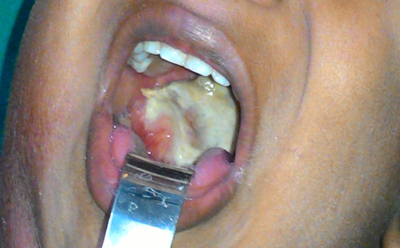

Diphtheria is caused by a bacterium called Corynebacterium Diphtheria. It mostly infects the throat and upper airways and produces a toxin that affects other organs. Symptoms start with a sore throat, fever, and chills, then the diphtheria toxin makes a thick white or greyish coating in the back of the nose or throat which makes it hard to breathe or swallow. The coating may get so thick that it blocks the airway and the person can’t breathe.